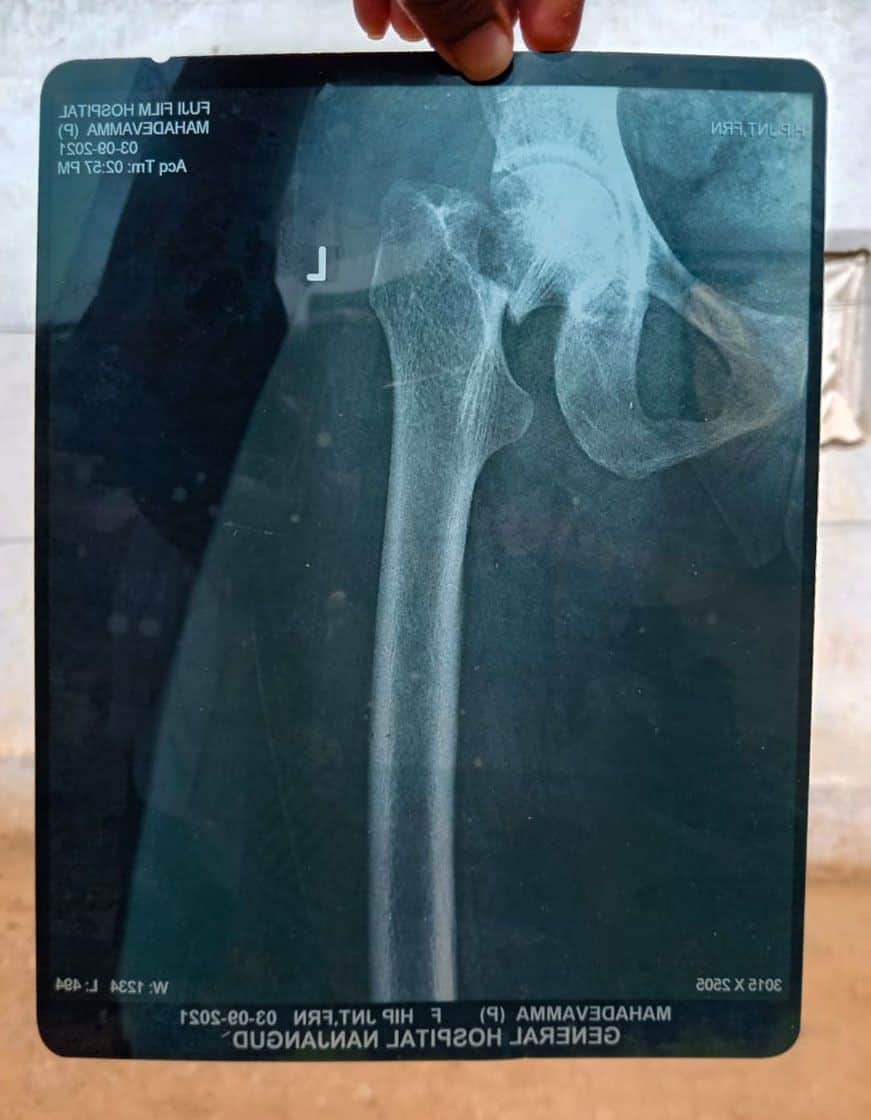

बाकिर अफसोस सुब्बैया के बरगद के गाछ भी बिका गइल, उहो खाली 8,000 रुपइया में. आपन घरवाली के इलाज खातिर उनकरा मजबूरी में ई सौदा करे के पड़ल. दू बरिस पहिले हब्बा (कर्नाटक के एगो त्योहार) के एक पखवाड़ा पहिले के बात बा. सुब्बैया के 56 बरिस के घरवाली बकरी चरावे निकलली. उहंई कवनो पत्थर पर गोड़ पड़ल, संतुलन गड़बड़ाइल आउर गिर पड़ली. गिरे से उनकर कूल्हा के हड्डी टूट गइल.

“हम बकरी के एगो बचवा के पाछू दउड़त रहीं. ऊ आपन झुंड से भटक गइल रहे. दउड़े घरिया पत्थर के ध्यान ना रहल. अइसन बेहिसाब गिरनी कि ठाड़े ना भइल जाए,” ओह बिपाद के इयाद करत महादेवम्मा कहली. “हमरा बहुते दरद होखत रहे. शुकर रहे कि उहंवा से जाए वाला लोग हमरा के उठा के घर पहुंचा देलक.”